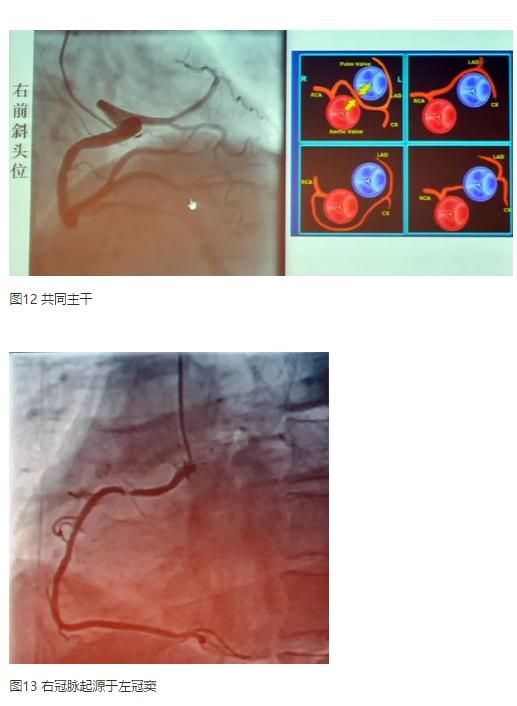

发现异常冠脉解剖结构

冠状动脉的异位起源常为主动脉或其他冠脉。起源于肺动脉者较为罕见,可影响心肌供血,有潜在危险,需外科治疗,多见于左主干、前降支或回旋支起源于肺动脉;冠脉分支起源异常的发生率低,仅0.4%。